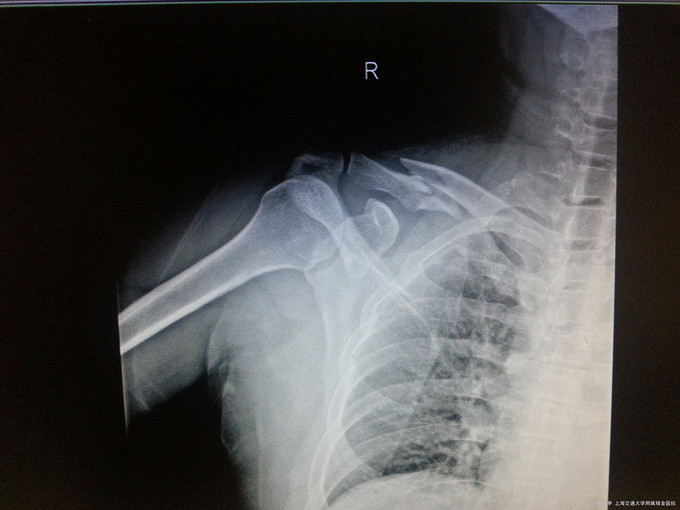

主诉:外伤后右肩部疼痛伴活动受限2天 病史: 患者,男,37岁。患者两天前踢球时与人冲撞,右肩部受撞击着地,当即感右肩部疼痛伴活动受限,未有向背部放射痛,右上肢及胸背部无皮肤破溃,未见活动性出血,远端肢体红润无苍白,无麻木感,手指活动可。摔倒前后无头晕头痛、恶心呕吐,无心悸、胸闷、呼吸困难等不适。伤后至我院急诊就诊,拍片示:右侧锁骨中段骨质断裂,并见斜形骨折线显示,断端错位明显,邻近软组织影肿胀,右侧肩锁关节间隙略增宽,予包扎固定治疗。现为进一步诊治,拟“右侧锁骨骨折”收治入本科。

查体:右肩关节轻度肿胀,右锁骨压痛,患侧关节活动受限,远端肢体感觉正常,右手指活动无异常,稍有麻木感。右上肢皮表无破溃及瘀血瘀斑。其余肢无明显异常。 辅查:右锁骨平片:右侧锁骨中段骨折,断端错位。

诊断:右侧锁骨骨折 处理:右锁骨骨折切开复位钢板螺丝钉内固定术